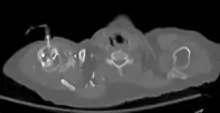

![]() The tibia IO insertion site is just below the medial condyle, labeled in this picture. | |

The needle is inserted through the bone's hard cortex and into the soft marrow interior, which allows immediate access to the vascular system. The IO needle is positioned at a 90 degree angle to the injection site, and is advanced through manual traction, impact driven force, or power driven. Each IO device has different designated insertion locations. The most common site of insertion is the antero-medial aspect of the upper, proximal tibia as this site lies just under the skin and is easily located. Other insertion sites include the anterior aspect of the femur, the superior iliac crest, proximal humerus, proximal tibia, distal tibia and the sternum (manubrium).[1] Although intravascular access is still the preferred method for medication delivery in the prehospital area, IO access for adults has become more common. As of 2010, the American Heart Association no longer recommends using the endotracheal tube (ET) for resuscitation drugs, except as a last resort when IV or IO access cannot be gained.[1] ET absorption of medications is poor, and optimal ET drug dosings are unknown. IO administration is becoming more common in civilian and military pre-hospital emergency medical services (EMS) systems globally.[11]